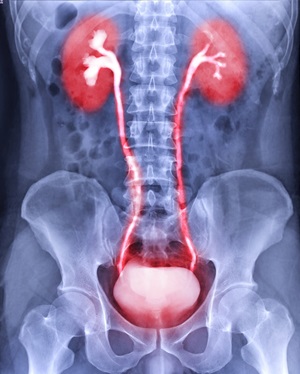

Cancer of the ureter is rare and occurs in the tubes that carry urine from the kidneys to the bladder and can also be found in the renal pelvis, the area where urine collects and is funneled into the kidney. Because ureter cancer is rare, you need urology experts who are experienced in treating this type of cancer.

Advanced testing by experienced urologists and uroradiologists is essential for a diagnosis of ureter or renal pelvis cancer. We use the latest imaging and digital ureteroscopy to make an accurate diagnosis.